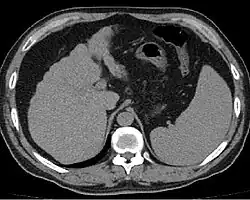

![]() Цирроз печени, приведший к гепатоцеллюлярной карциноме (макропрепарат) | |